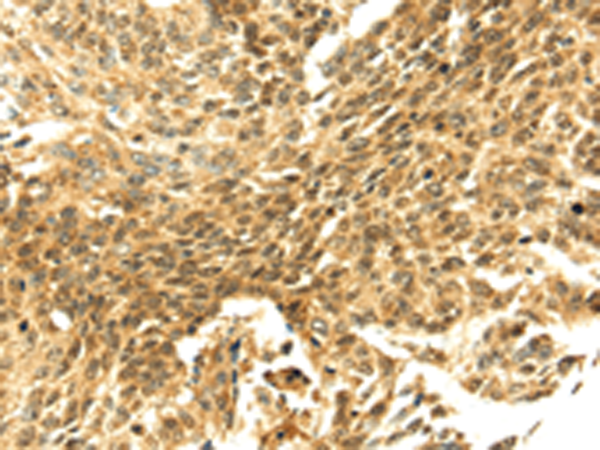

分类: 科研抗体货号: P08765别名: bA545I5.2应用: IHC反应种属: Human, Mouse